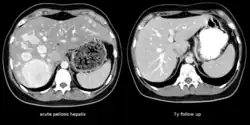

Peliosis hepatis

Mit Peliosis hepatis wird ein Krankheitsbild der Leber bezeichnet, welches durch blutgefüllte Zysten gekennzeichnet ist. Diese Zysten entstehen durch den Untergang von Lebergewebe (parenchymatöse Form) oder durch Aussackung der Zentralvene des Leberläppchens (phlebektatische Form).